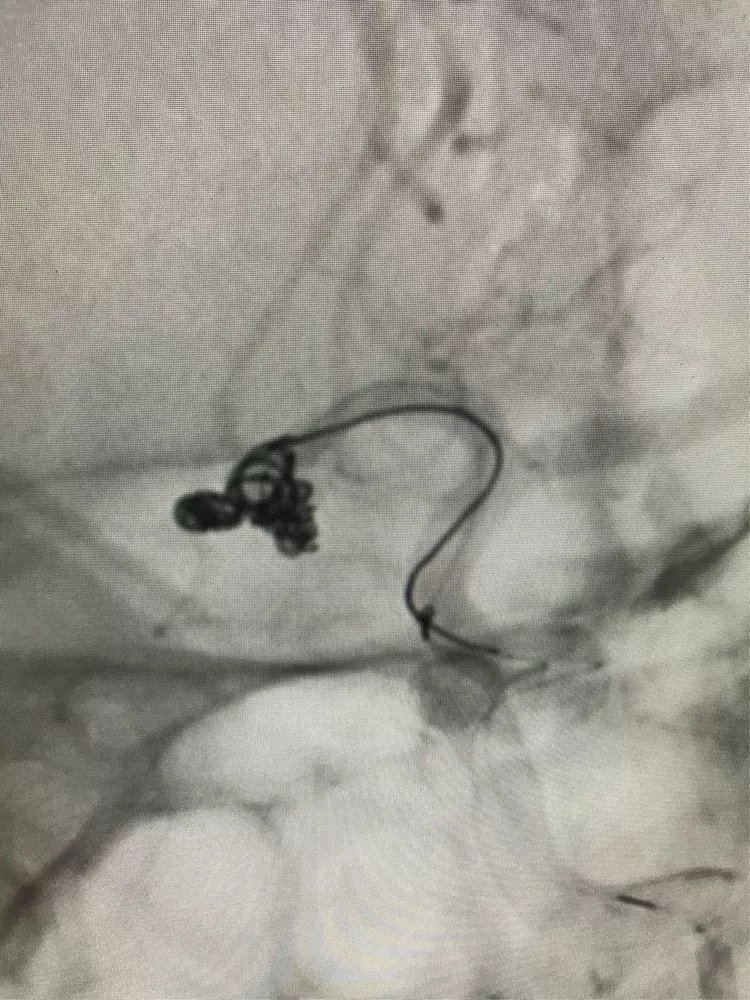

在弹簧圈的辅助下,对2号子瘤进行填塞。

看看辅助后的填塞效果。

继续2号子瘤的填塞(还是主瘤内弹簧圈辅助,填完后我想看看效果,就把辅助的弹簧圈又回收了。)